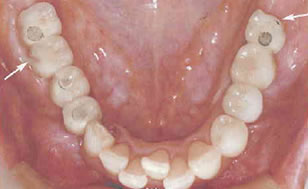

ブラキシズムへの配慮が欠け、次々と歯が破折し、歯を失っていった例

|  |  |  |  |  |

| 矢印の歯が破折。 | やむをえず抜歯した。 | 次に隣の歯が破折し、抜歯した。 |